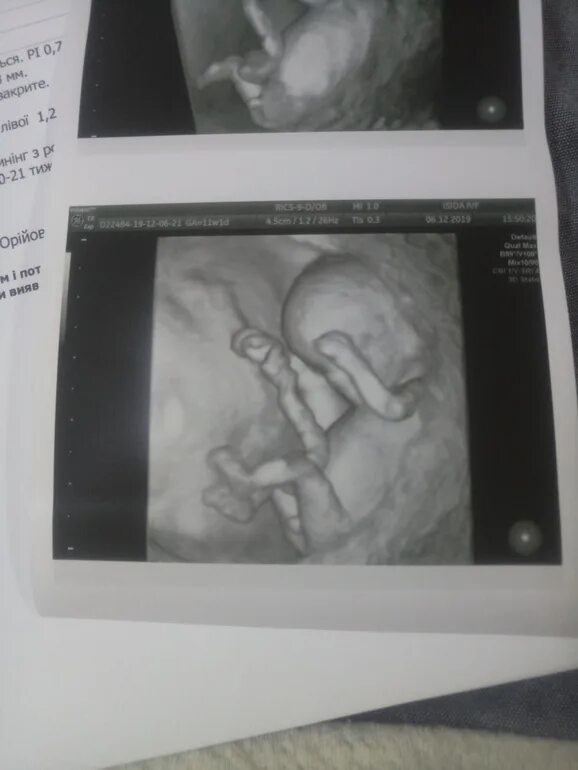

Скрининг 10